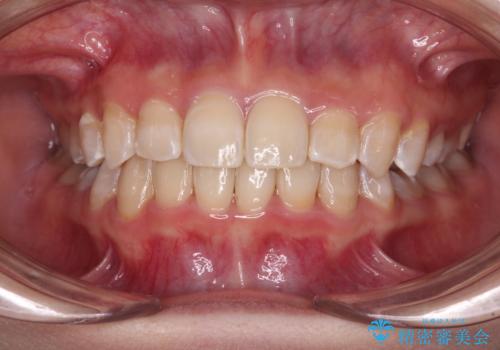

30代女性 前歯のがたつき